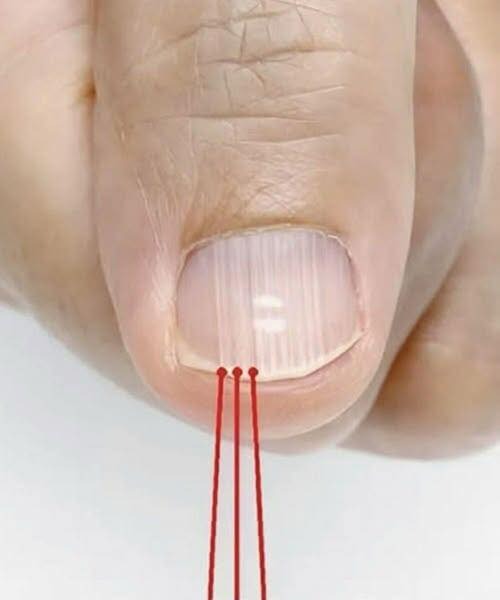

Ti stai lavando le mani. Le stai asciugando. E all’improvviso, te ne accorgi: 👉 Delle linee sottili che vanno dalla cuticola alla punta dell’unghia, come morbide rughe incise sulla superficie.

Prima non c’erano. O almeno, non erano così evidenti.

Per molte persone, queste creste verticali sulle unghie compaiono gradualmente con l’età, silenziosi indicatori del tempo che passa, proprio come le rughe sottili sulla pelle o i fili d’argento nei capelli.

Sebbene sia naturale chiedersi: “C’è qualcosa che non va?”, nella maggior parte dei casi la risposta è no.

Esploriamo cosa significano realmente le creste verticali, perché si formano e quando potrebbero segnalare qualcosa di cui vale la pena parlare con un medico.

Perché la vera salute non consiste nel ricercare la perfezione. Si tratta di capire la storia del proprio corpo, una cresta alla volta.